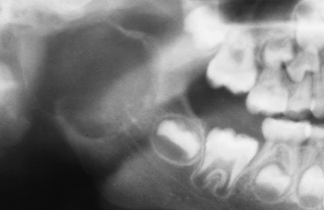

cleidocranial dysplasia

pt also has hypoplastic clavicles